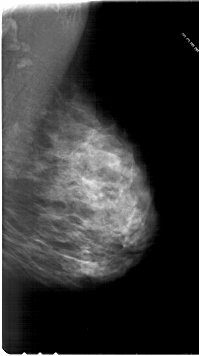

A_1814_1.LEFT_MLO

LEFT_MLO LINES 6316 PIXELS_PER_LINE 3586 BITS_PER_PIXEL 12 RESOLUTION 43.5 OVERLAY